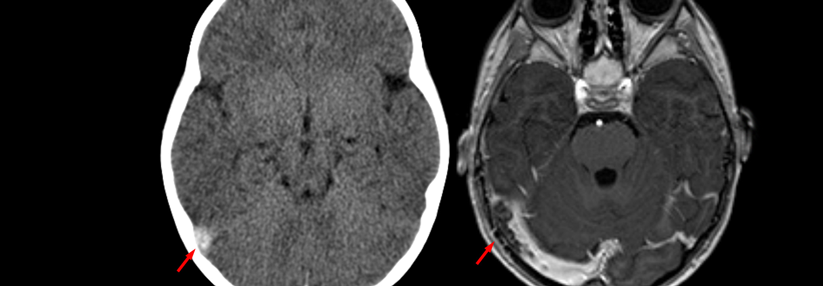

CT ohne und MRT mit Kontrastmittel zeigen beide den Befund einer SVT (Pfeil) beim selben Patienten.

CT ohne und MRT mit Kontrastmittel zeigen beide den Befund einer SVT (Pfeil) beim selben Patienten. © wikimedia/Hellerhoff